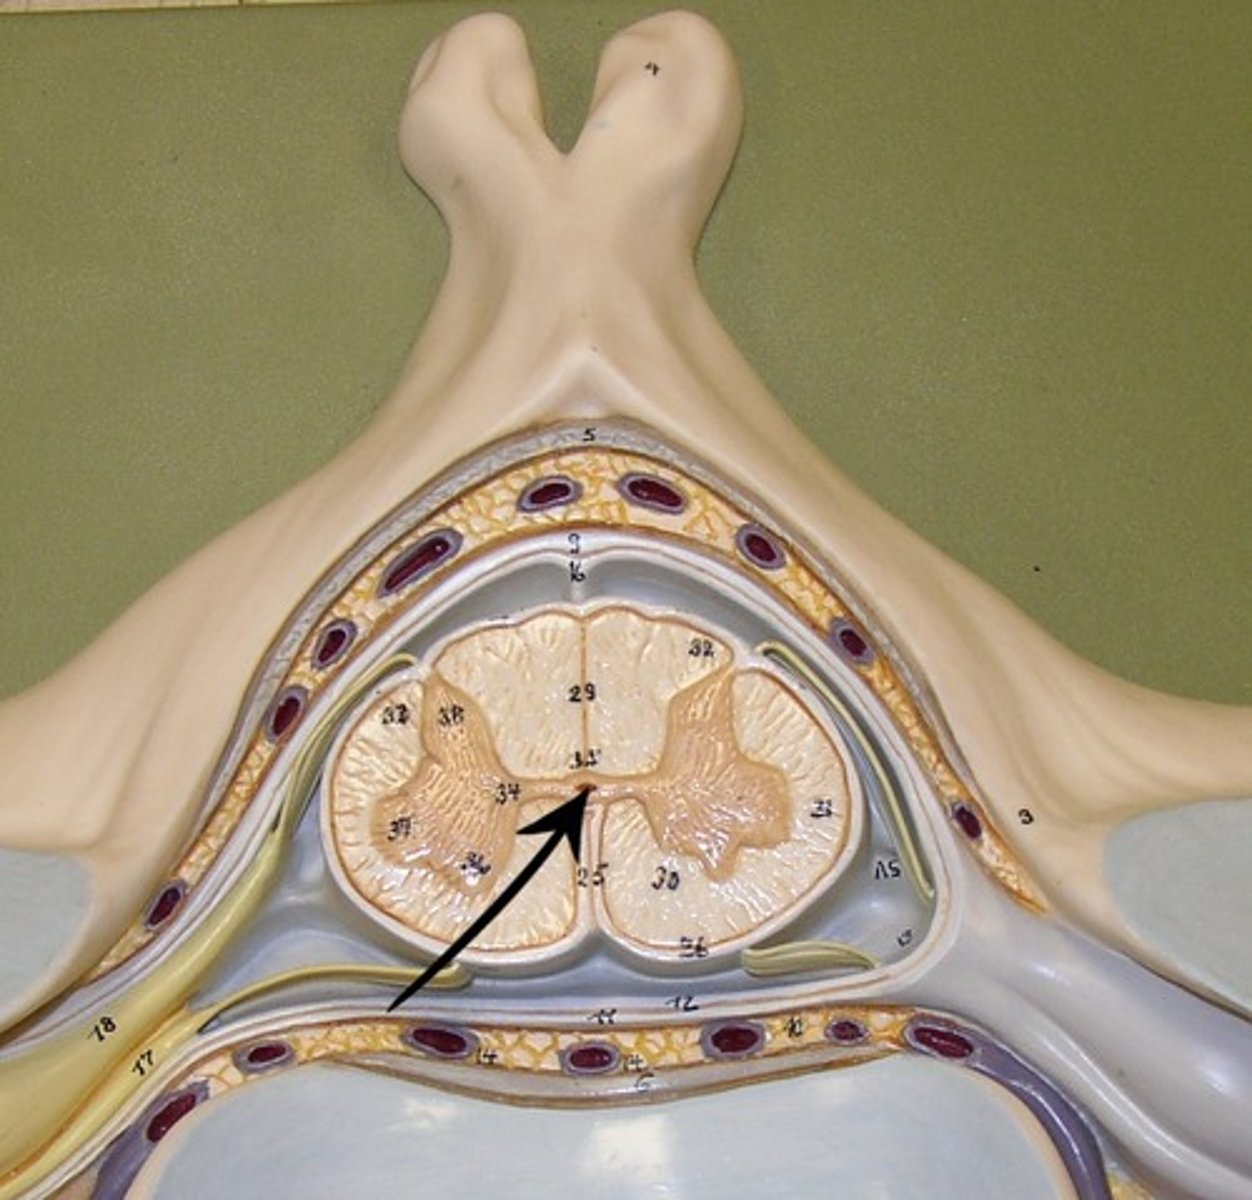

gray commissure

Part of grey matter connecting the two halves of the grey matter in spinal cord

posterior gray horn

anterior gray horn

lateral gray horn